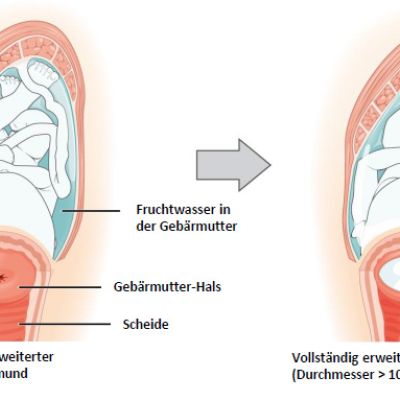

Schematische Darstellung einer Geburt in 3 Phasen: